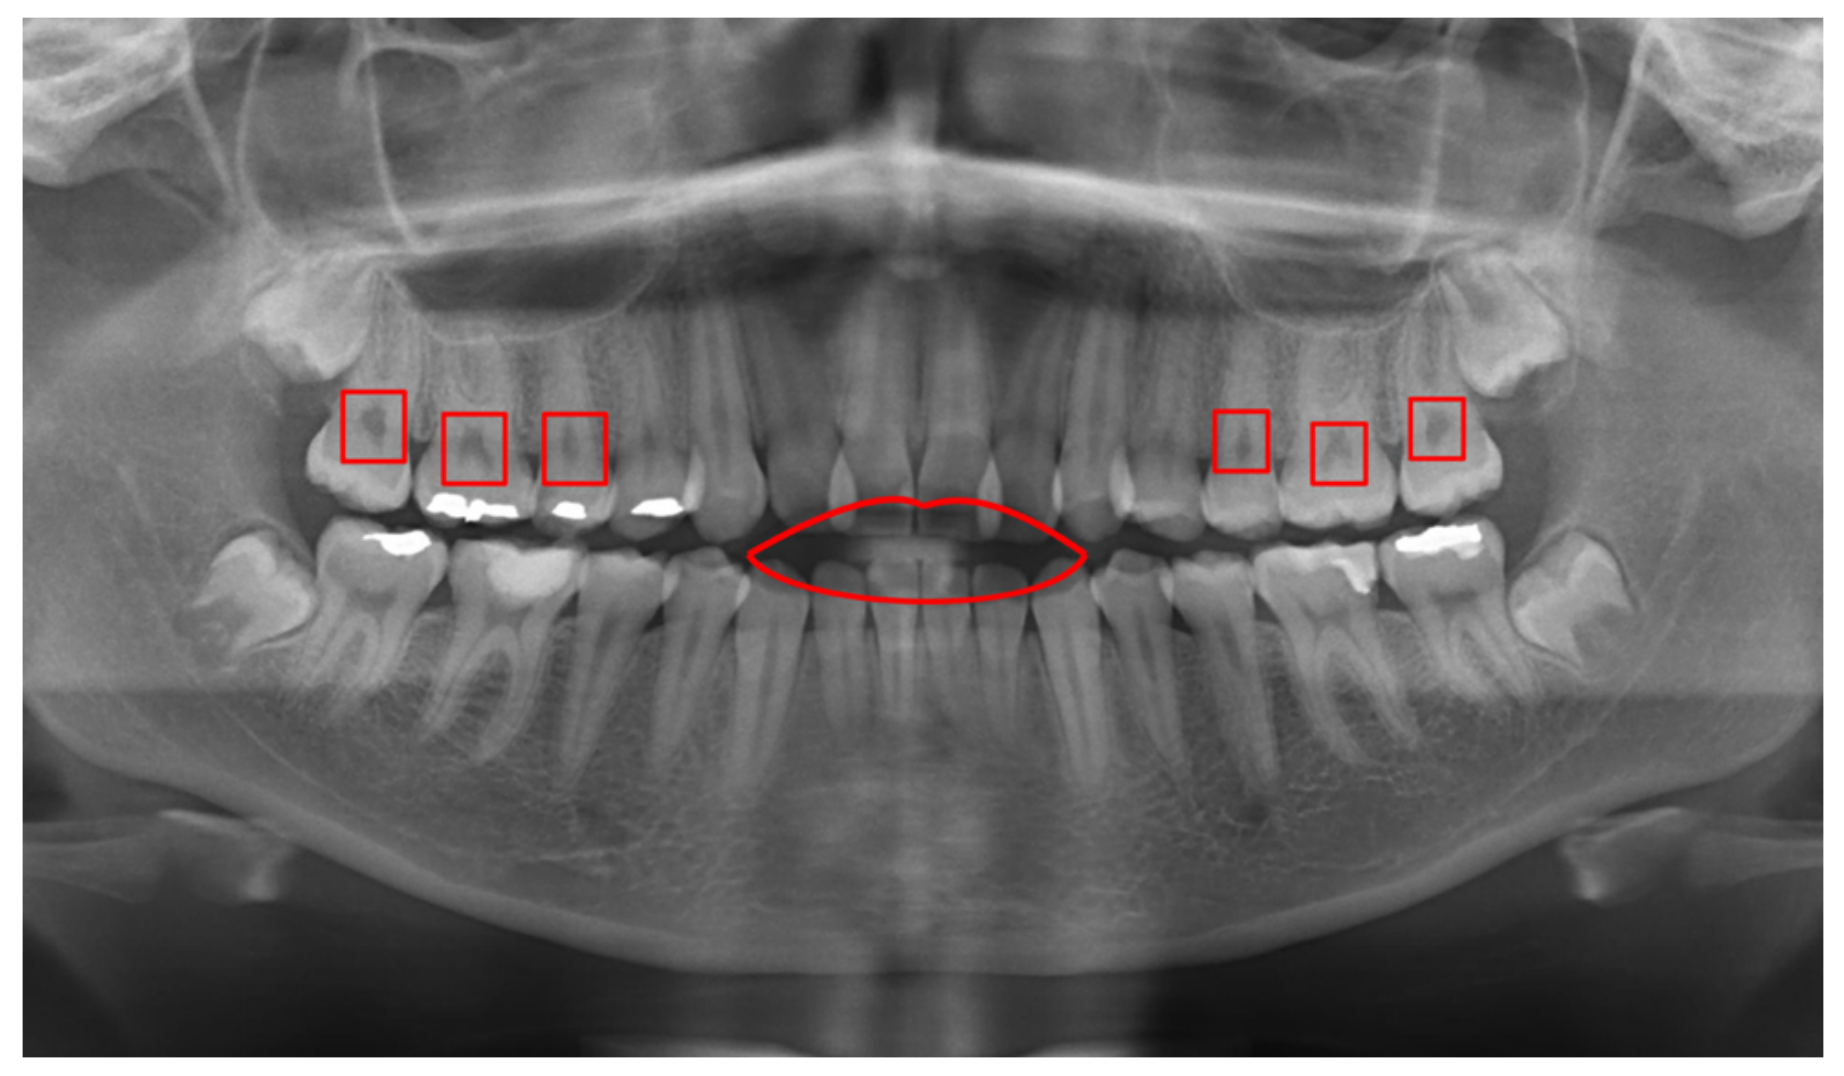

From www.mdpi.com

Applied Sciences Free FullText Detection of Cavities from Dental Dental Panoramic X Ray Cpt Code  This guide is published to educate dentists and others in the dental community on selection and reporting of diagnostic imaging procedures. Code on dental procedures and nomenclature effective january 1, 2022 d0367 cone beam ct capture and interpretation with field of view of. The d0220 dental code, officially recognized by the american dental association (ada), refers to the procedure for.. Dental Panoramic X Ray Cpt Code.

Applied Sciences Free FullText Detection of Cavities from Dental Dental Panoramic X Ray Cpt Code  This guide is published to educate dentists and others in the dental community on selection and reporting of diagnostic imaging procedures. Code on dental procedures and nomenclature effective january 1, 2022 d0367 cone beam ct capture and interpretation with field of view of. The picture shows all the. D0210 is typically paid once every three to five years. A radiographic. Dental Panoramic X Ray Cpt Code.

Applied Sciences Free FullText Detection of Cavities from Dental Dental Panoramic X Ray Cpt Code  The picture shows all the. The d0220 dental code, officially recognized by the american dental association (ada), refers to the procedure for. Code on dental procedures and nomenclature effective january 1, 2022 d0367 cone beam ct capture and interpretation with field of view of. This guide is published to educate dentists and others in the dental community on selection and. Dental Panoramic X Ray Cpt Code.